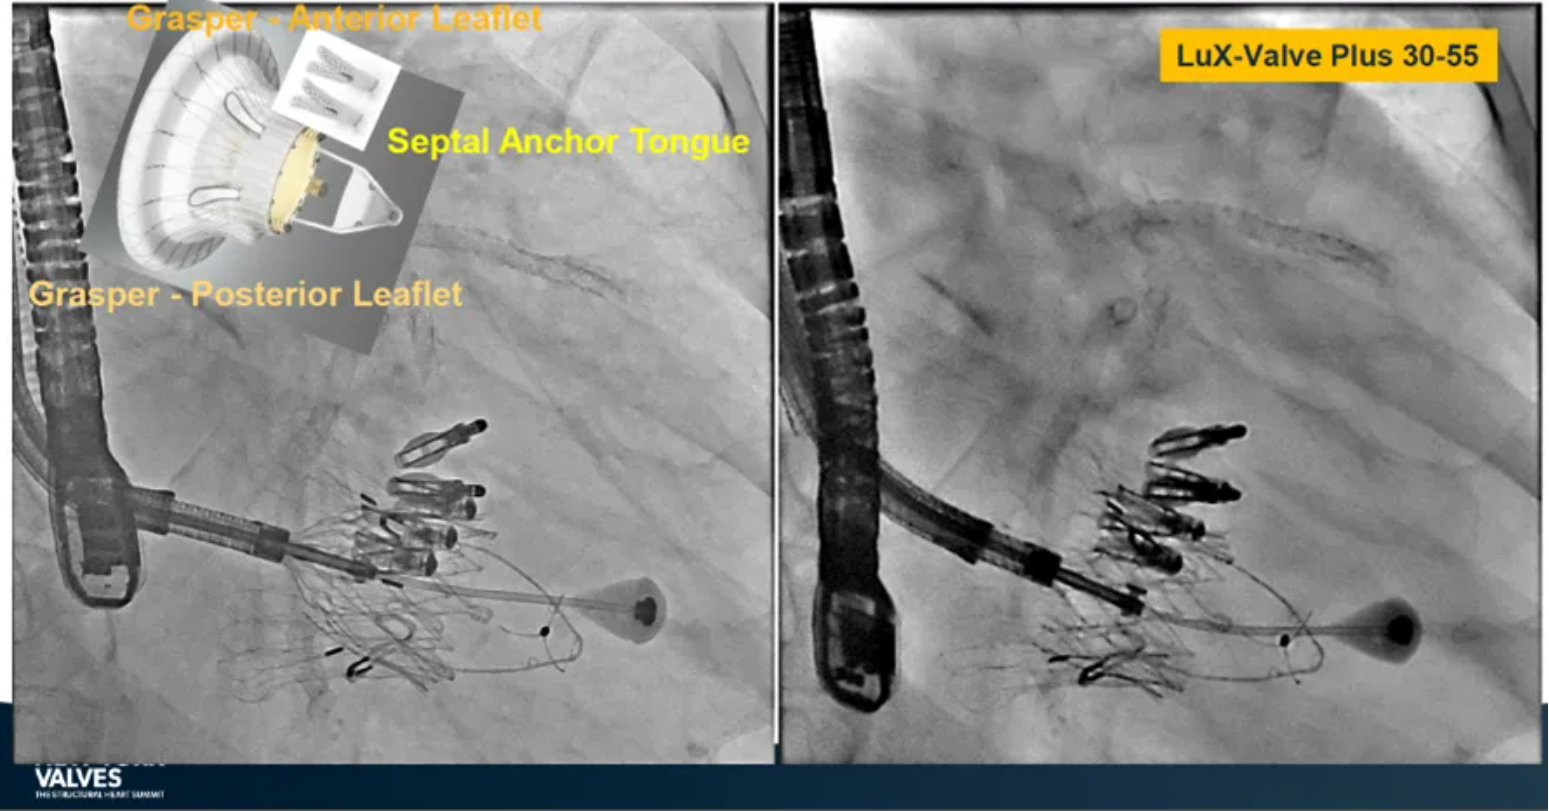

LuX-Valve Plus是健世科技(Jenscare,9877.HK)推出的全新一代經(jīng)頸靜脈三尖瓣置換系統(tǒng)(Transjugular Tricuspid Valve Replacement System),其創(chuàng)新性地采用頸靜脈作為手術(shù)入路,在不依賴徑向支撐力的情況下借助室間隔錨定、瓣葉夾持技術(shù)構(gòu)成其多重錨定結(jié)構(gòu),并通過自適應(yīng)編織環(huán)有效進行心房側(cè)封堵,呈現(xiàn)更好的安全性和有效性。

來自中國香港瑪麗醫(yī)院(Queen Mary Hospital, Hong Kong, China)的Simon Lam教授在2024年紐約瓣膜會上分享了一例復(fù)雜案例,一名高齡男性患者在2年前行二尖瓣和三尖瓣TEER術(shù)式后繼發(fā)三尖瓣反流,遂再次行二尖瓣TEER術(shù)式和用LuX-Valve Plus行三尖瓣TTVR術(shù)式。

本次術(shù)式中,LuX-Valve Plus的植入緊隨二尖瓣修復(fù)術(shù)式之后,且并未取出前期植入的三尖瓣修復(fù)夾,這意味著LuX-Valve Plus在患者有過二尖瓣和三尖瓣修復(fù)夾植入情況下的兼容性,并且?guī)砹擞行У闹委熃Y(jié)果。此外,這不僅體現(xiàn)了LuX-Valve Plus可以與二尖瓣術(shù)式并行,更可以兼容三尖瓣原位的其他修復(fù)夾產(chǎn)品。